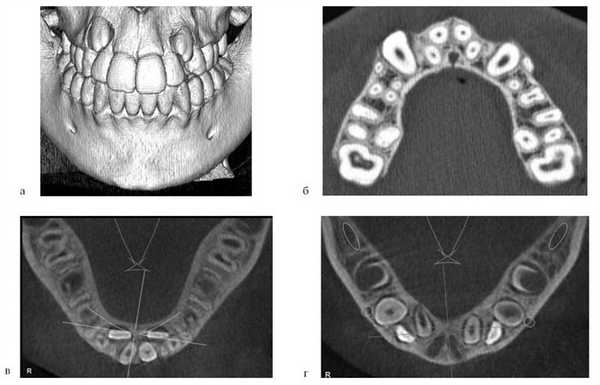

Ортодонтическое лечение после костной пластики проводилось под контролем за состоянием аутотрансплантата с помощью дополнительных методов диагностики — ЭОМ, УЗИ, спиральной компьютерной томографии (СКТ), что позволило оценить степень остеоинтеграции, либо резорбции костного регенерата (рис. 3).

Рис. 3. СКТ: 3D-реконструкция (а), аксиальный срез через 4 года после костной аутопластики (б), выделенный объем костного регенерата (в).